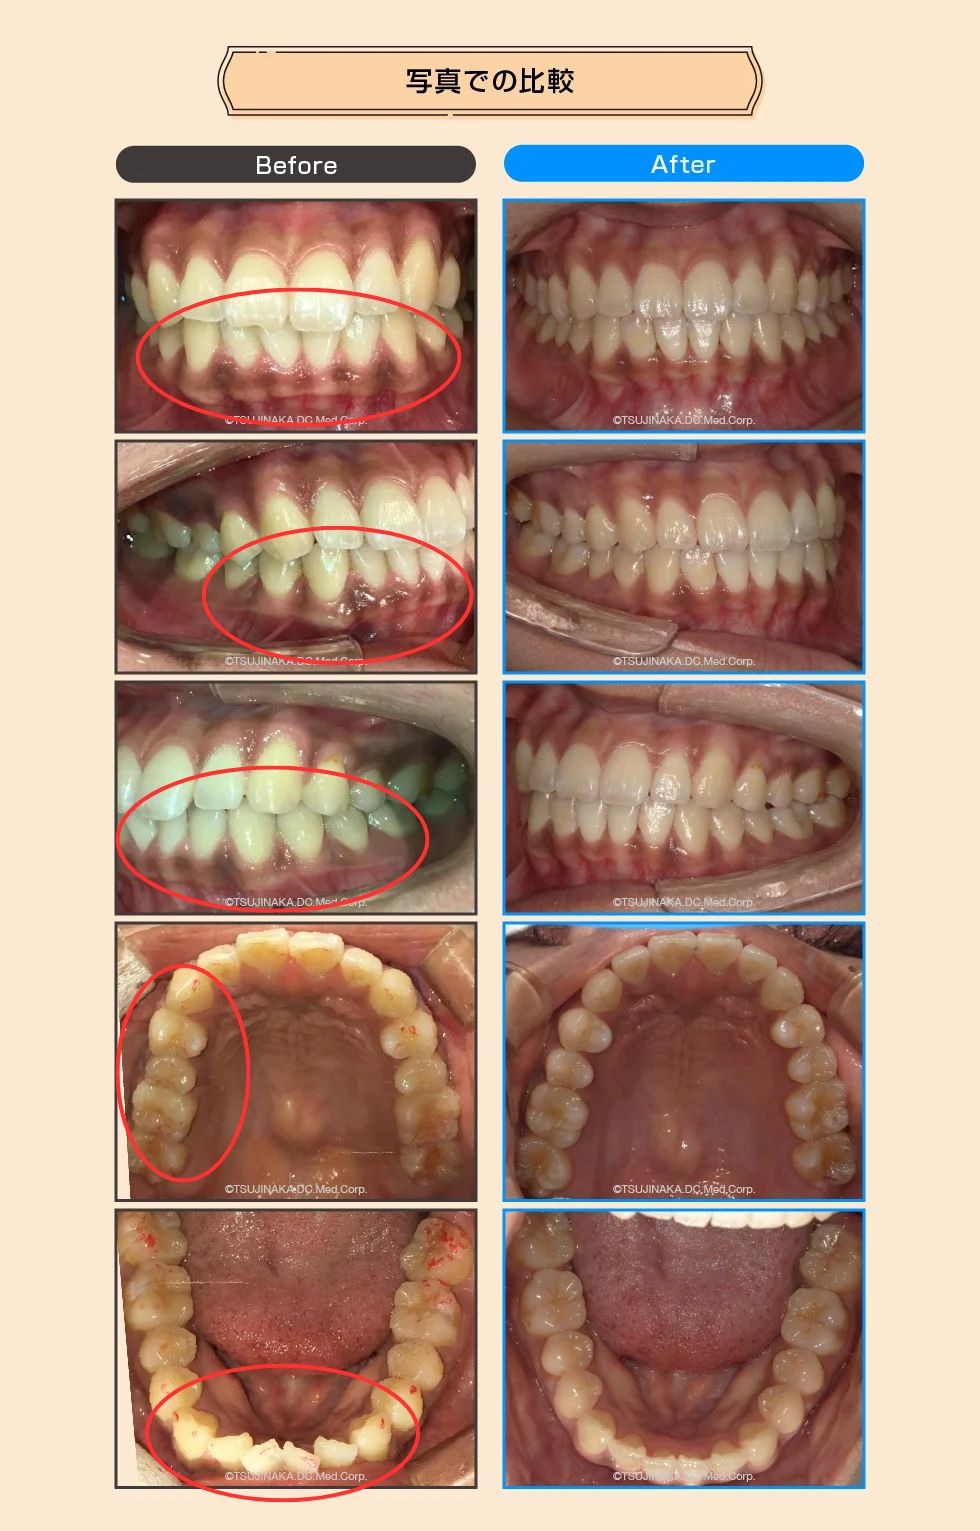

【症例No.7197】噛み合わせが強いせいで骨が隆起している

噛み合わせが強いせいで骨が隆起している

歯並びのデコボコや噛み合わせの違和感が気になるとのことでご相談いただきました。マウスピース型矯正装置を用いた矯正治療により、歯列の改善を目指し、歯の移動に伴う歯肉の変化にも配慮しながら進めました。

| 主訴 | 歯並びのガタつきと噛み合わせの違和感が気になる(骨のふくらみが心配) |

| 診断名 | 下顎叢生 |

| 治療内容 | マウスピース型矯正装置(インビザライン)を用いた矯正治療。歯列の改善を目指し、歯肉退縮などのリスクに配慮しながら経過を確認して進めました。 |